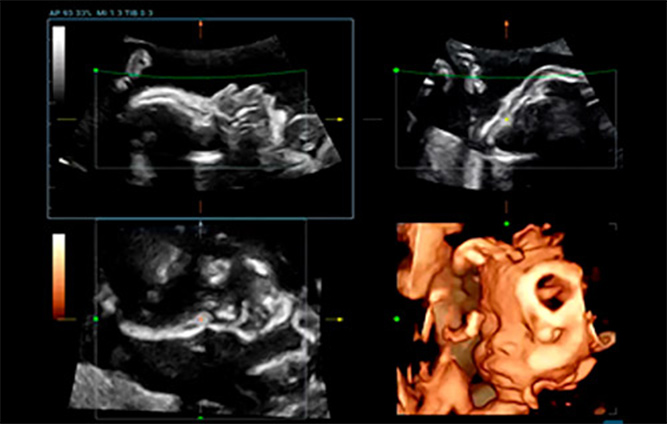

Sin embargo, la baja eficiencia del examen de ecografĆa del feto, en diversos sitios y mediciones, ha preocupado a los ecografistas durante mucho tiempo. El examen de ecografĆa 3D/4D otorga gran importancia al diagnĆ³stico ultrasĆ³nico del feto, que puede proporcionar a los mĆ©dicos la ubicaciĆ³n espacial de las estructuras con mĆ”s detalle. Sin embargo, el cambio de posiciĆ³n y movimiento del feto, el complicado ajuste de los parĆ”metros y los engorrosos pasos operativos afectan significativamente la calidad y la eficiencia. Durante mucho tiempo, hemos reflexionado sobre cĆ³mo mejorar la consistencia y la repetibilidad del examen de ecografĆa 3D para obtener un diagnĆ³stico preciso.

Para reducir la dependencia del usuario y mejorar la eficiencia del diagnĆ³stico, Mindray desarrollĆ³ una innovadora interacciĆ³n 3D/4D basada en situaciones clĆnicas para contextos tĆpicos de exĆ”menes de ecografĆa 3D (como los del cerebro, el rostro, la columna vertebral y los huesos largos del feto). Esta soluciĆ³n permite la identificaciĆ³n automĆ”tica de escenas, la optimizaciĆ³n automĆ”tica de las imĆ”genes, la captaciĆ³n automĆ”tica de planos y la cuantificaciĆ³n automĆ”tica con un solo clic. Realmente hace posible un flujo de trabajo automĆ”tico durante todo el procedimiento, lo que otorga una fuerte confianza en el diagnĆ³stico para una mejor atenciĆ³n del paciente.

Smart Planes CNS

Smart ICV: CƔlculo automƔtico del volumen intracraneal

Smart Face

ImĆ”genes de ecografĆa 3D/4D de la columna fetal